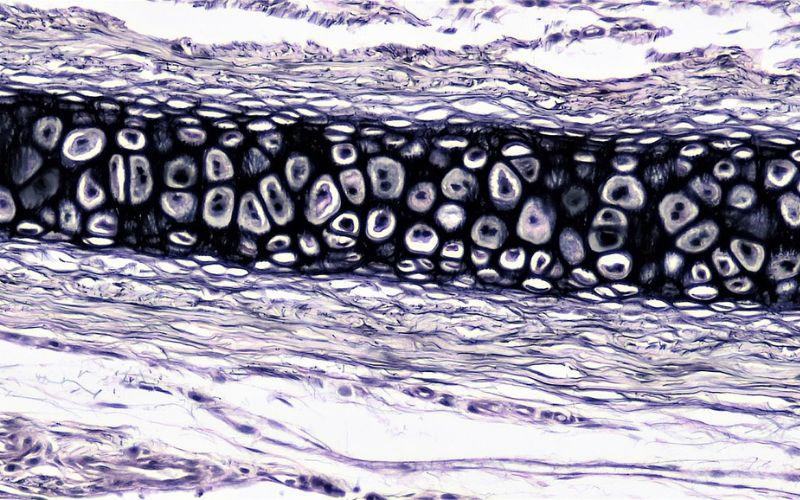

– Estructura microscópica. Bajo el microscopio, revela una red de condrocitos ubicados en lagunas dentro de la matriz extracelular. Las fibras elásticas se entrelazan en la matriz, aportando la elasticidad característica.

– Composición. Está formado por tipos celulares llamados condrocitos, incrustados en la matriz extracelular. La matriz contiene fibras elásticas, principalmente elastina, que le confieren la elasticidad característica a este tejido. Esta matriz es sólida y flexible.